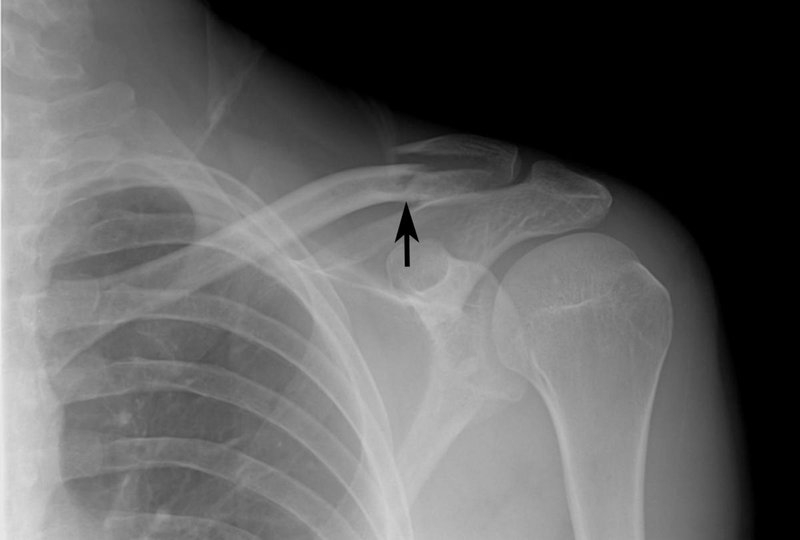

Nguyên nhân gãy xương đòn vai? Các phương pháp điều trị

Gãy xương đòn vai (hay được gọi là xương quai xanh) là một trong những chấn thương thường gặp hiện nay. Bất kỳ tác động nào đến vùng vai đều có thể làm tổn thương và gãy xương ở khu vực này. Bài viết dưới đây, nhà thuốc Long Châu sẽ giải đáp về vấn đề nguyên nhân gãy xương đòn vai và các phương pháp điều trị hiệu quả.

Xương đòn vai hay còn gọi là xương quai xanh nằm giữa lồng ngực và bả vai có tác dụng như một thanh chống, cho phép khớp vai có thể hoạt động với cường độ tối ưu. Ngoài ra, xương đòn còn có chức năng bảo vệ một số cấu trúc quan trọng ở phía dưới như phổi, đám rối cánh tay, bó mạch dưới đòn…

Theo thống kê, có khoảng 80% các trường hợp gãy xương đòn vai là do chấn thương gián tiếp ngã đập và chống tay với tư thế dạng. Trường hợp gãy xương đòn vai trực tiếp chiếm khoảng 20% và hầu hết là chấn thương hở.

Nguyên nhân gãy xương đòn vai? Các phương pháp điều trị 1 Gãy xương đòn xảy ra do nhiều nguyên nhân khác nhau với mức độ nghiêm trọng khác nhau